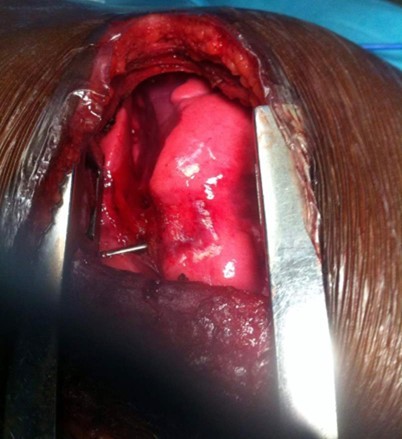

AD, aged 10, with no particular pathological history, was referred to us for the management of a post-traumatic intrapulmonary foreign body. The traumatism would have occurred one month earlier, during a playful accident. He would have received from his brother, at the level of the left hemithorax, a blow with the metal tail of a comb. The latter would then have been torn off by the child but without the tail. This would have caused a minimal wound, associated with an intense chest pain, without dyspnea, or cough, justifying local care and treatment with analgesics. The incident was withheld from parents. On admission, there was a punctiform scar in the 2nd left intercostal space, about 5 cm from the sternal border. The pulmonary fields were free. The rest of the exam was normal. The biological results were normal. A first chest x-ray showed a metal rod, oblique downwards, backwards and inwards, going from the 5th to the 11th left costal arch (Figure 1). The computed tomography scan of the chest showed the metal rod in the lung parenchyma. It was approximately 105 mm long and stayed away from the heart and the great vessels. There was no pulmonary parenchymal abnormality, pleural effusion or obvious bone lesion (Figure 2). Two subsequent X-rays showed its migration downwards, inwards and backwards with an upper pole sitting opposite the posterior arch of the 8th rib. A left posterolateral thoracotomy approach allowed the removal of the metal rod lodged in the lower lobe of the lung (Figure 3). The postoperative period was unremarkable. The ablation of the drains was carried out on the5th postoperative day. The patient was discharged on the 8th day. Reviewed in the6th postoperative month, his examination was normal.

Figure 3.Foreign body visible within left lower pulmonary lobe through posterolateral thoracotomy